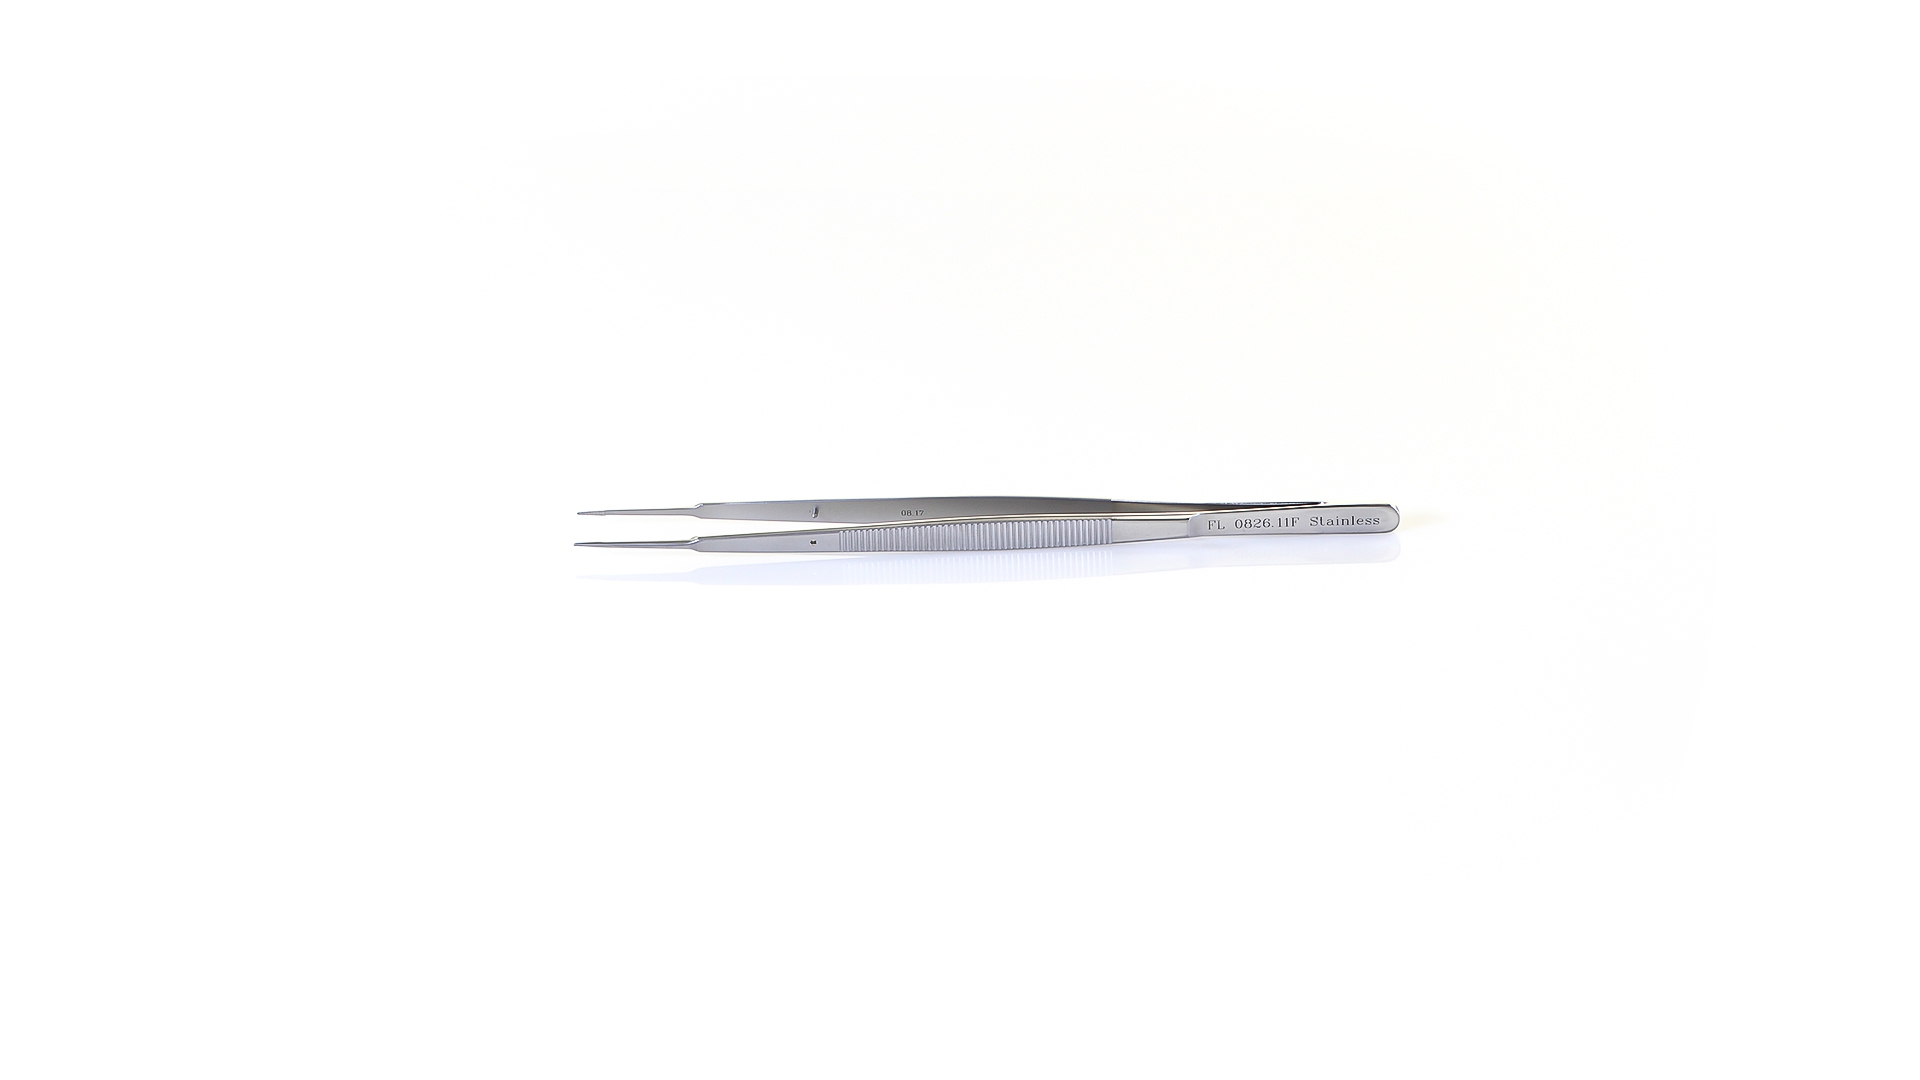

Item number: FL0826.11F

Gerald Platform Forceps - Straight 0.7mm TC coated tips, Flat Handle, Stainless Steel, 7.25'' (18.5cm)

| Instrument Type | Gerald Platform Forceps |

| Tip Size | 0.7mm |

| Tip Type | Platform |

| Tip Shape | Straight |

| Tip Interior | TC coated |

| Handle Configuration | Spring Forceps |

| Handle Type | Flat (8.5mm) |

| Hinge Bar | Standard |

| Total Length | 7.25" (18.5cm) |

| Material | Stainless Steel |